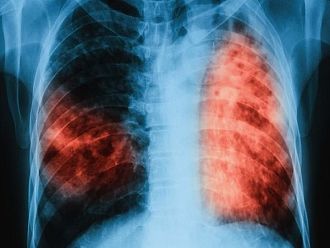

Туберкулоза е лечимо и предотвратимо заболяване, стига да бъде открито навреме и да бъде проведено съвременно лечение с необходимата продължителност, напомнят от МЗ. Ранното откриване на туберкулозата и започване на своевременно лечение в дългосрочен план води до намаляване на случаите. Въпреки значителните успехи, постигнати в борбата с туберкулозата в Европейския регион на СЗО, тя продължава да представлява заплаха за общественото здраве.